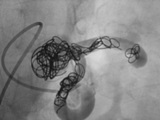

Coil的主要困难在第一个和最后一个弹簧栓子。以及非常有挑战的困难病例。 第一个弹簧栓子放置的困难性在于如何适合靶血管的大小与形状。往往需要在术前精确地测量CT或/和血管造影,除了选择形状相应的弹簧栓子外,还要选择适合靶血管的血流,若对于高血流病变选择微弹簧栓子很难达到安全的栓塞。高血流的AVM需要在静脉一侧植入超大的弹簧栓子,使用球囊导管阻止或减少血流,用更长和更大的可脱弹簧栓子(0.035~0.038)。要么就找个分支“锚定”吧! 最后一个弹簧栓子的困难性,在于如果弹簧栓子太长、太大,靶血管已经填塞完成,多余的部分栓子无处可置,如果是可控的可脱式弹簧栓子,若为推送式弹簧栓子则可能发生并发症。如何知道和如何确保最后一个弹簧栓子不至于过长和过大。主要是要决定每次栓塞的终点。弹簧栓子填塞的%,预期所需栓子的大小和量,用球囊和支架辅助栓塞避免弹簧栓子移位。或用较少的弹簧栓子,添加液体栓塞剂如NBCA或Onyx。 弹簧栓子的困难病例主要包括解剖困难,比如所栓塞靶血管为短段,可以置放弹簧栓子范围太小,短段或靶血管痉挛。血管入路非常扭曲,特别是需要导管内腔较大或弹簧栓子导丝直径较大的时候,比如需要20mm直径的弹簧栓子阻塞较大的动静脉瘘,导丝的直径为0.042。血管迂曲和弹簧栓子太长可能导致弹簧栓子难以推动。除了困难的解剖,病人的情况好坏也是具有挑战队一件事。 栓塞肺动静脉畸形时要避免空气进入静脉,撤出导丝时应在盐水内进行。尽量接近动静脉瘤囊的位置实施截面闭塞(cross section occlusion,CSO)。术后需要使用抗菌素。肝素应用带有纤毛的可脱式弹簧栓子,考虑充分的肝素化,因为不必要的血凝块可能导致动脉系统的栓塞。而栓塞精索静脉曲张或盆腔充血综合征在有硬化剂辅助下不需要截面闭塞。

截面闭塞 cross section occlusion

不充分填塞(Inadequate packing)主要用于慢血流的血管畸形的栓塞或在高速血流的情况下减慢血流速度联合其它液体栓塞剂的应用。也可作为静脉血管的阻塞,比如动静脉畸形的静脉流出道的阻塞。而致密填塞(Dense packing),又称截面栓塞(Cross-Section Occlusion,CSO)主要用于出血,动脉瘤囊填塞,血流导向或肺动静脉畸形的栓塞等应用。对于肺动静脉畸形,CSO尽可能接近动静脉畸形巢或囊。精索静脉曲张或盆腔充血综合症不需要CSO技术,特别是在配合硬化剂的情况下。